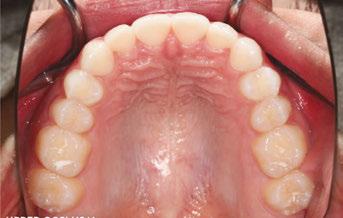

Figures 6 through 9 demonstrate a patient successfully treated with NiTime Aligners following the patient’s rejection of other systems. Figures 6 and 8 display pre- and posttreatment photos of a patient that presented with a Class II malocclusion and normal OB/OJ. This patient has teeth Nos. 7 and 10 missing congenitally. Note that the patient was treated as a child and has a canine substitution due to the missing lateral incisors. Recession was noted on tooth Nos. 2,3, 4, 5, 9, 11, 13, 14, 22, 24, 26, and 27. The patient tried labial and lingual brackets unsuccessfully, as well as a leading clear aligner to correct her malocclusion as an adult. In all three treatments, the patient could not tolerate the mechanics due to increased discomfort and was unable to complete therapy.

It is important to note that there was no refinement required for this case, and the patient finished in 26 weeks with 26 trays. Although the patient presented with significant recession, it did not worsen with treatment. As demonstrated in Figure 9, teeth aligned as planned by the OrthoFX treatment plan shown in Figure 7. Overlays of the actual results with the original treatment plan indicate a high level of predictive accuracy. Not only was a satisfactory result produced from the patient wearing the aligners, but the accuracy is quite high for the NiTime material despite the patient wearing it significantly less than the traditional 22 hours per day.

Figure 6: Class II malocclusion pretreatment

Figure 8: Class II malocclusion posttreatment. Left column pretreatment. Right column posttreatment 22 stages

Figure 7: Predicted results from the OrthoFX treatment plan